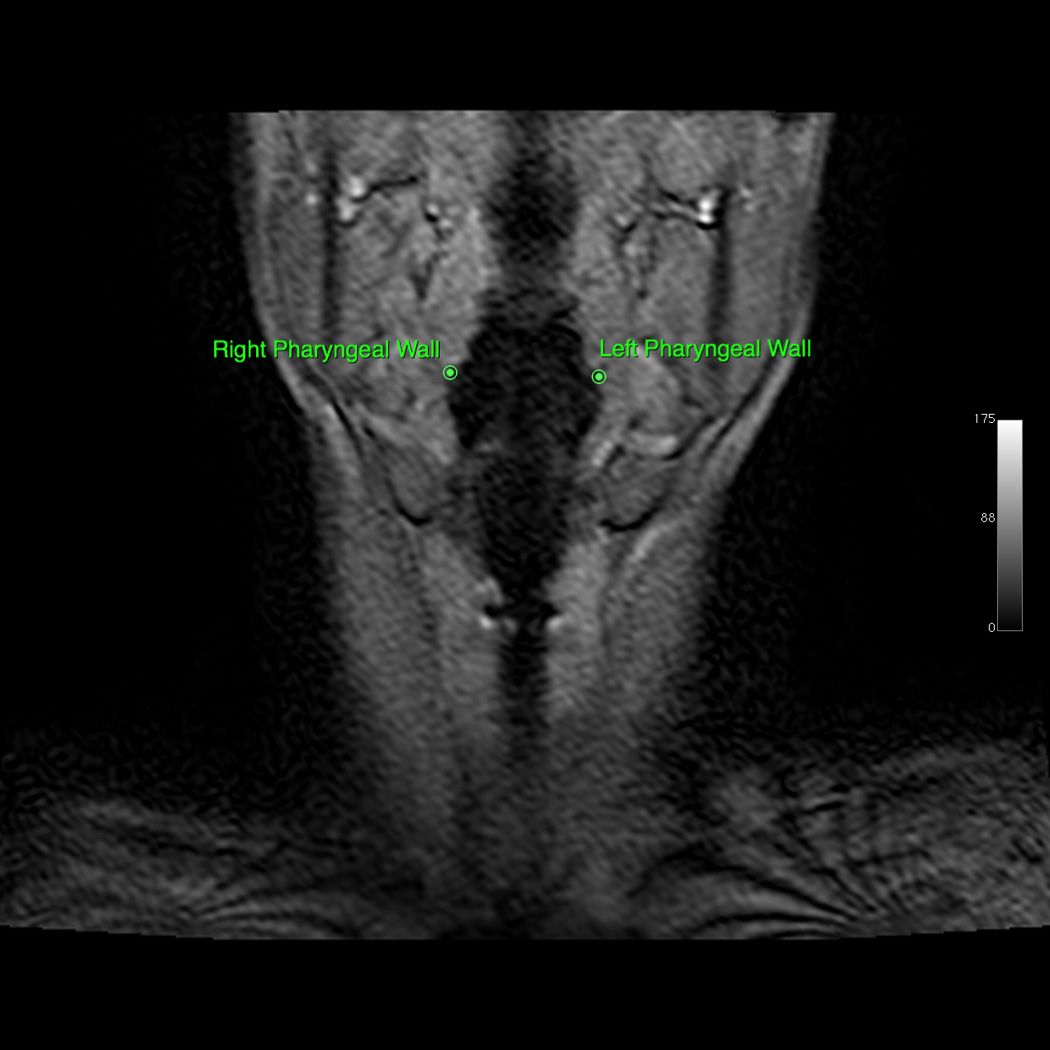

Osirix digital imaging and communication in medicine software was used to produce digital QuicktimeTM videos of dynamic MRI swallows and EPG (www.osirix-viewer.com). Image J image analysis software was used to collect coordinate data of anatomical landmarks from the digital video files (http://rsbweb.nih.gov/ij). From the sagittal image, coordinates of anatomical landmarks tracking the movement of the hyoid, larynx, and pharyngeal walls were collected at rest and at maximum excursion for both the repeated swallowing task and EPG. Minimum and maximum hyolaryngeal excursion among all dynamics (frames) were selected for measurement to ensure that the dynamic range of movement was characterized. Anatomical landmarks included the mandible (inferior mental spine), the posterior edge of the hard palate, the tubercle of the atlas (as a proxy for the styloid process in the lateral view), the anterior inferior edge of C2 and C4, the anterior superior edge of the hyoid, the anterior commissure of the vocal fold, the posterior attachment of the vocal fold, and the most inferior point of the air column in the hypopharynx proximal to the upper esophageal sphincter (UES; see Figure 2, Panels A–D). From coronal images, coordinates of anatomical landmarks mapping pharyngeal wall medialization were measured at the level of the arytenoids for both the repeated swallowing task and EPG (see Figures 3, Panels A–D). Coordinates mapping anatomical landmarks were used to calculate excursion measurements in centimeters for swallowing and EPG, including anterior and superior hyoid movement, hyolaryngeal approximation, laryngeal elevation, and pharyngeal shortening in the midsaggital plane and pharyngeal wall medialization in the coronal plane (see Figure 4). A speech-language pathologist and anatomist measured all subjects independently for interrater reliability.

Figure 3.

A: Coronal view of minimum hyolaryngeal excursion during EPG. B: Coronal view of maximum hyolaryngeal excursion during EPG. C: Coronal view of minimum hyolaryngeal excursion during swallowing. D: Coronal view of maximum hyolaryngeal excursion during swallowing. a. Coronal view of minimum hyolaryngeal excursion during effortful pitch glide

Regarding medialization of the lateral pharyngeal walls, the EPG elicited a similar effect compared with the swallow. In this study, pharyngeal wall medialization moved a mean of 1.81 cm for the EPG compared with a mean of 2.29 cm during the swallow, which was not significantly different (p = .16). During deglutition, the contraction of the pharyngeal constrictors medialize the pharyngeal walls to propel the bolus through the pharynx (Langmore, 2001). Medialization of the lateral pharyngeal walls has been documented during the PSM (Bastian, 1993; Fuller et al., 2009). The upper lateral walls of the pharynx form portions of the superior pharyngeal constrictors that also contribute to closure of the velopharynx during phonation (Sumida, Yamashita, & Kitamura, 2012). In addition to the pharyngeal constrictors, the palatopharyngeus muscles contribute to the contraction of the lateral pharyngeal walls during phonation tasks (Sumida et al., 2012). The combined contraction of the pharyngeal constrictors and palatopharyngeus muscles may account for the similarities shown during the EPG and the swallow for medialization of the lateral pharyngeal walls.